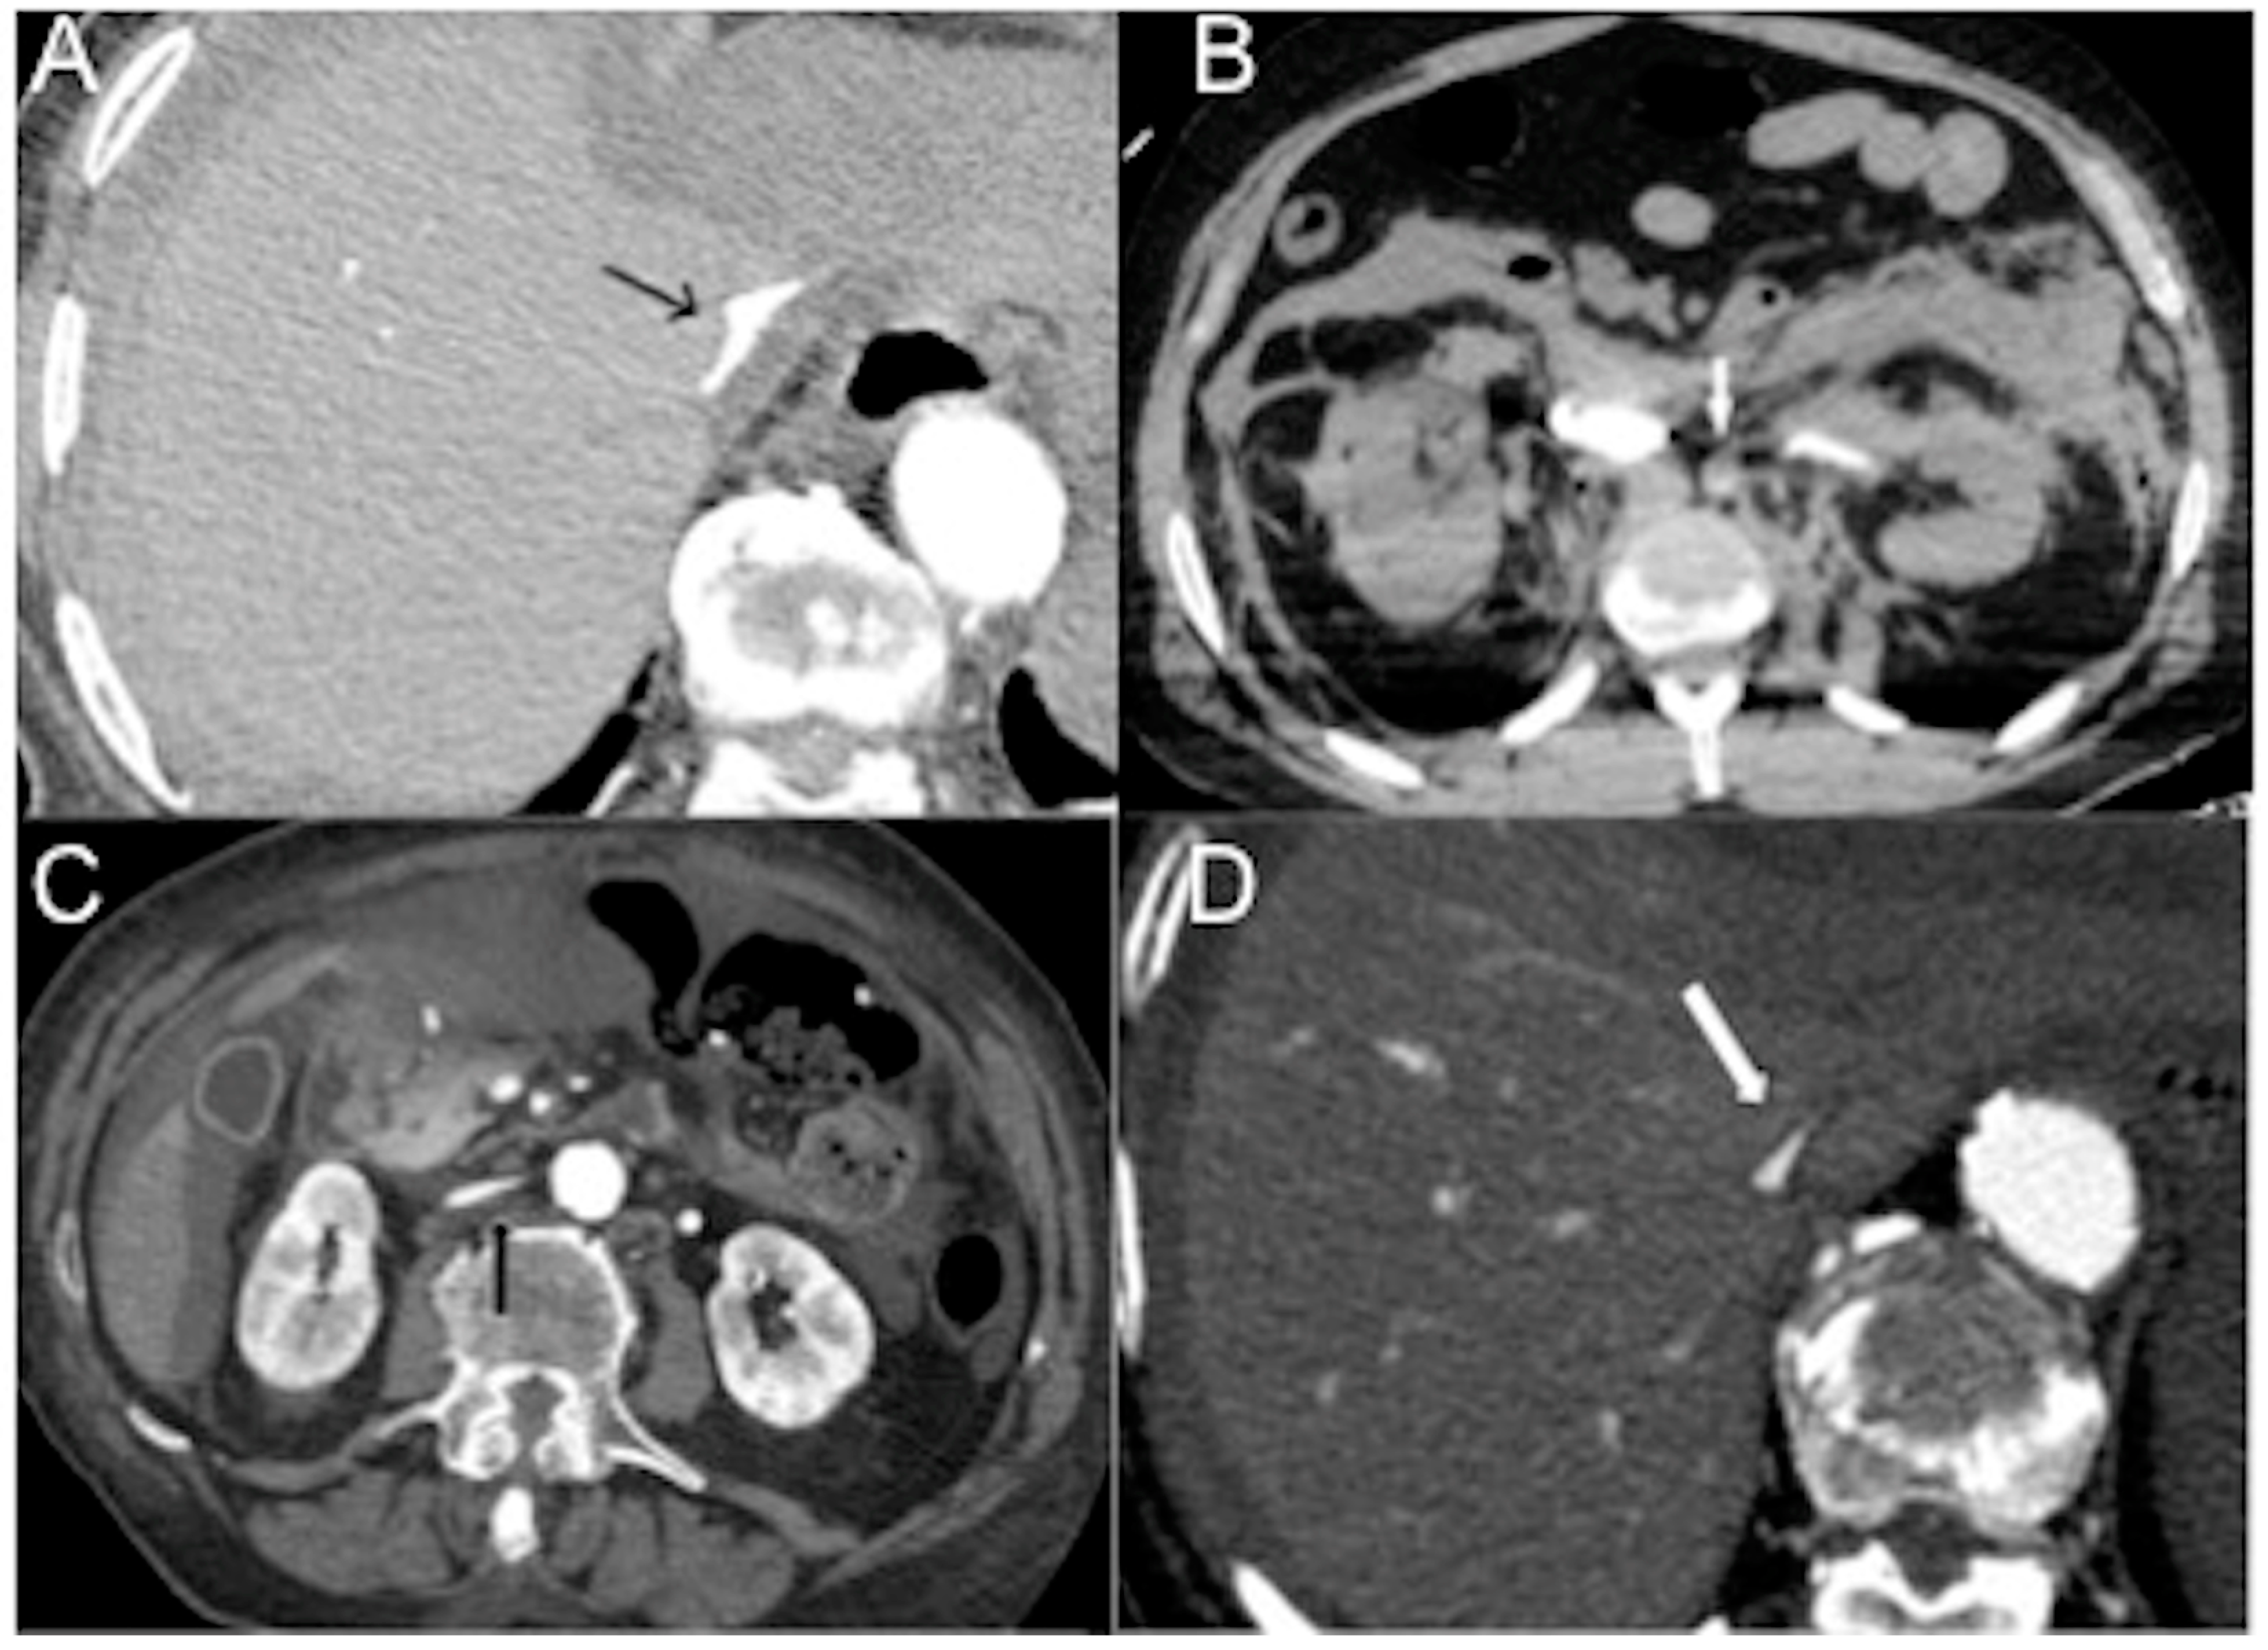

- There is the presence of a slit-like or flat inferior vena cava (FIVC) (Figure 2A). This is characterized by an anterior-posterior diameter of less than 9 mm in three consecutive segments, 20 mm above and below the renal veins, and at the level of the perihepatic region. Additionally, a transverse-to-anteroposterior ratio of ≥2.5 at the level of the suprarenal IVC can indicate flattening. The flatness index or IVC diameter ratio is calculated by dividing the maximal transverse and anteroposterior diameters of the IVC [15,16,17,18,19,20,21,22,23,24,25,26,27,28,29,30,31,32,57,58,59,60,61].

- Flattening of the IVC (slit sign) is often seen in cases of decreased circulating blood volume (hypovolemia) and indicates reduced venous return in patients with systemic hypotension. However, it may not be easily appreciated due to the administration of large volumes of fluids [31]. This finding is more commonly observed in acute hypovolemic traumatic patients. Variations in intra-abdominal pressure and the respiratory cycle can also affect the diameter of the IVC. IVC flattening has a specificity of 90% and a sensitivity of 84% in identifying hypo-perfusion shock in spontaneously breathing patients [15,16,17,18,19,20,21,22,23,24,25,26,27,28,29,30,31,32,57,58,59,60,61,62,63]. The IVC diameter ratio measured via CT scans can help predict in-hospital mortality in septic shock patients, with a cut-off value of ≥1.3 cm having 75% sensitivity and 42% specificity [63]. It is also useful in determining the amount of blood transfusion required and assessing the volume status of patients with blunt torso trauma. [64].

- The IVC halo sign is characterized by a low attenuation band (<20 HU) encircling the collapsed intra- and retrohepatic inferior vena cava. This band is caused by a ring or rim of edema [65,66,67]. In cases of severe hypovolemia, approximately 80% of patients may exhibit this sign, resulting from the loss of precapillary arteriolar sphincter tone and the accumulation of fluid surrounding the IVC (Figure 2B–D) [18,25,30,31,65,66,67]. However, it is important to note that this sign is not specific to non-traumatic patients and can also be observed in conditions such as liver congestion, biliary cirrhosis, hepatitis, or other diseases that obstruct lymphatic drainage at the porta hepatis [25].